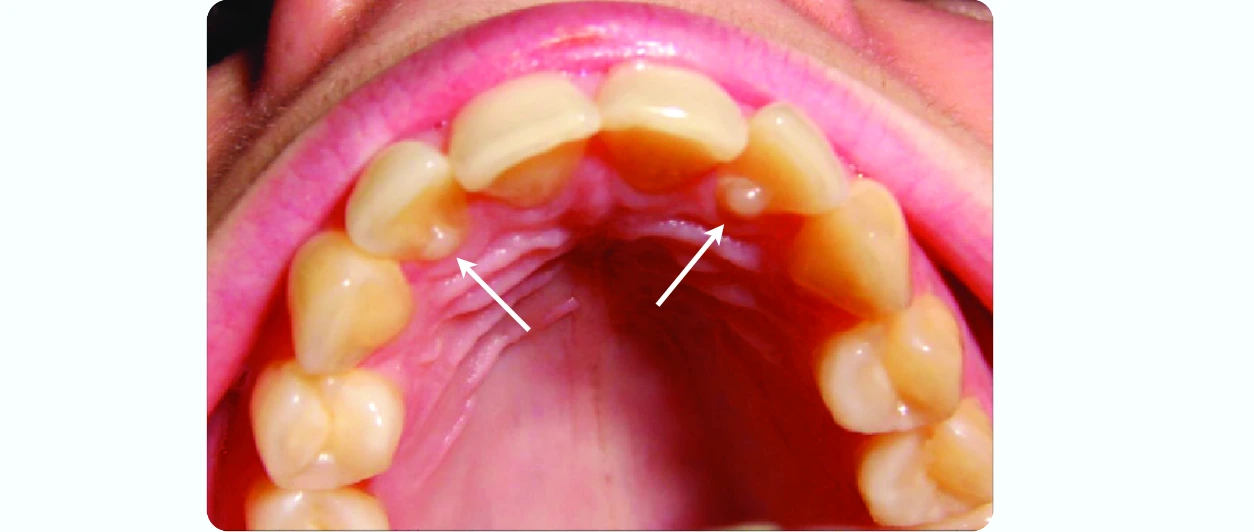

Mamelons

These are small, rounded protuberances found on the incisal ridges of newly erupted permanent incisor teeth.

- They are three in number and represent the mesial, labial and distal lobes on incisor teeth.

- As the teeth are used for mastication, the mamelons wear off and disappear.

Image: Mamelons in the anterior teeth of a 14 year old patient with an open bite. Source: Wikimedia Commons. Author: Shaimaa Abdellatif